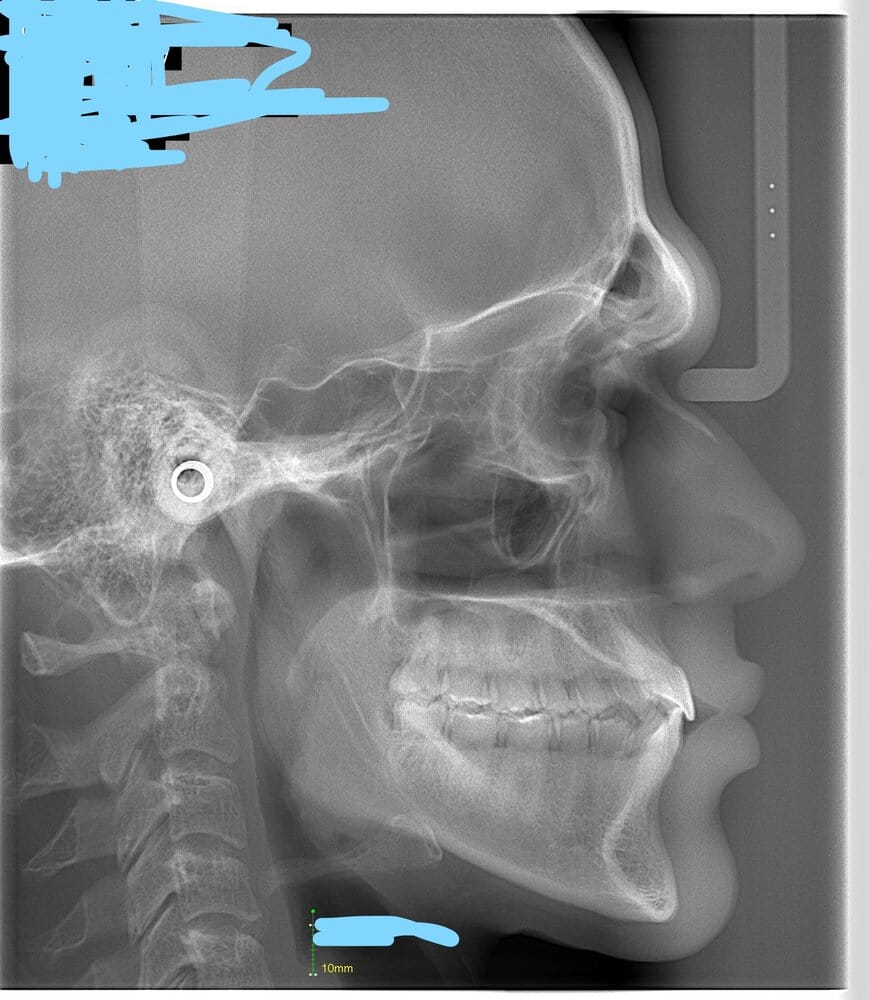

Here's the cephalogram i had:

btw looking at your ceph yes u need CW not CCW, look at your hyoid bone is so up, your submental must be like 90 degree or even 80

When doing surgery for short face always CW

Your cephalometric x-ray looks great.. but it's impossible to tell from an x-ray only, it's just a small part of the picture.